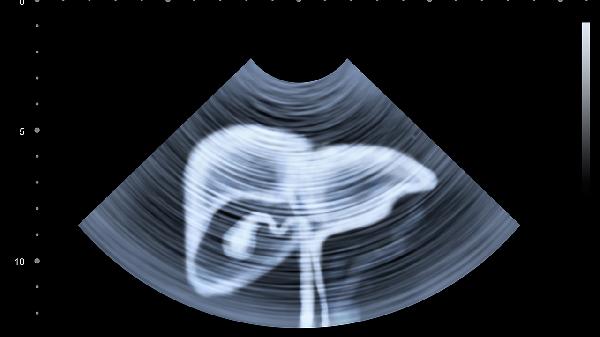

建议保持每日三餐定时定量,选择煮熟的燕麦、南瓜等低纤维食物过渡。疼痛期间暂停咖啡、碳酸饮料等刺激性饮品,用温水袋热敷腹部15-20分钟。若症状持续超过1周或出现呕血、体重下降等警示症状,须立即就医进行胃镜或腹部超声检查。夜间睡眠时可抬高床头15厘米减少胃酸反流。